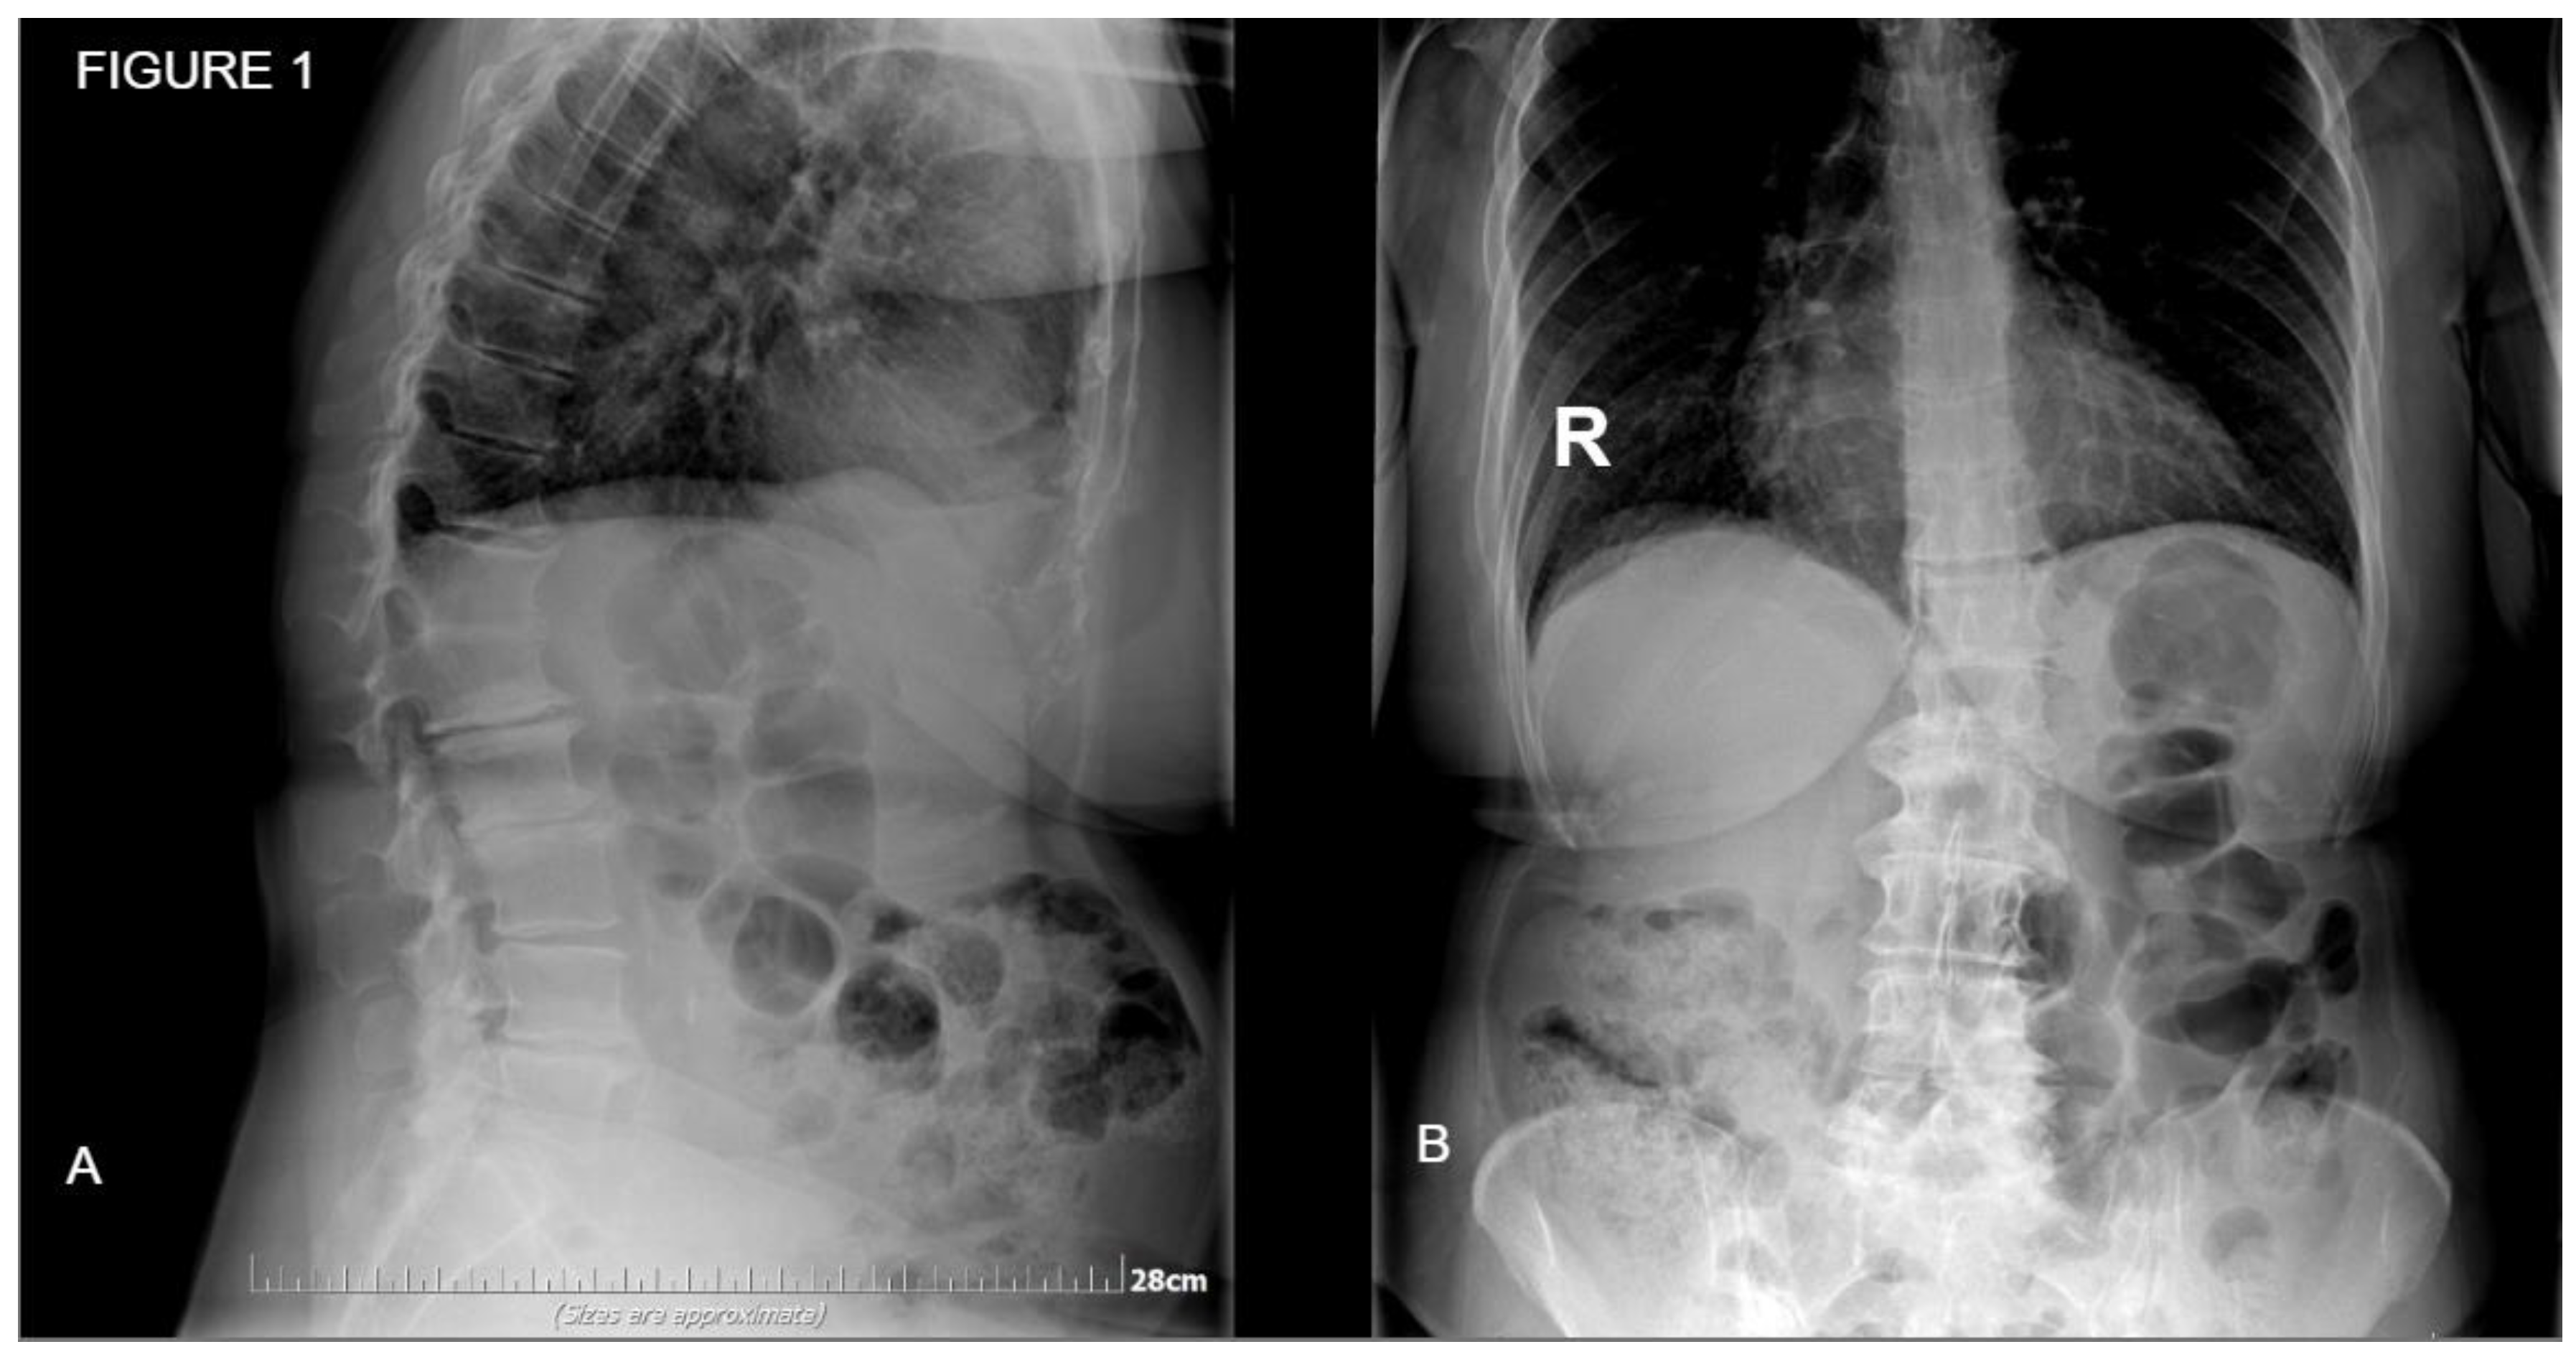

Figure 2. Postoperative standing x-ray of the same patient from Figure 1. A: Sagittal place demonstrating satisfactory amount of lordosis and disc height. B: Coronal plane of the posterior fixation and interbody fusion.